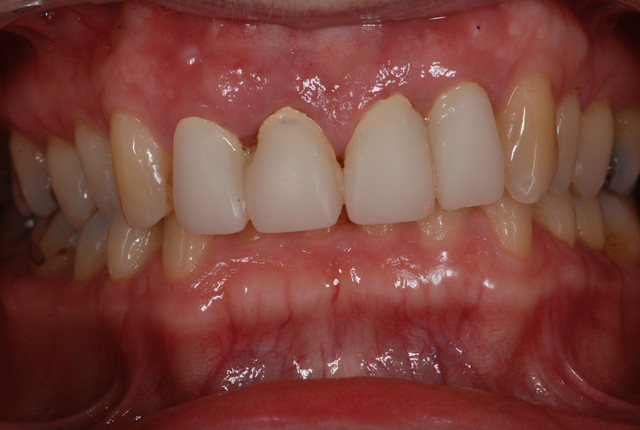

E.max crown try in 280713

#Togias 190713 nora